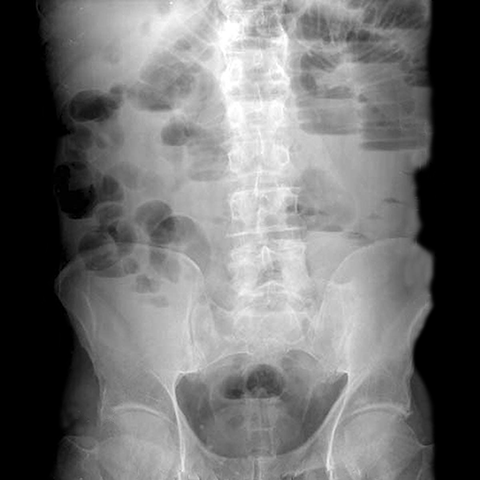

27 year-old male with a history of an appendectomy presents with nausea, vomiting, colicky abdominal pain, and diarrhea. [2 of 3]